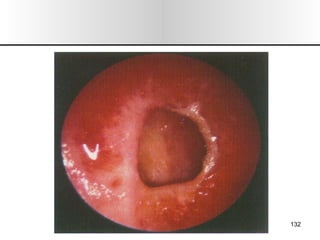

Nariz y senos paranasales